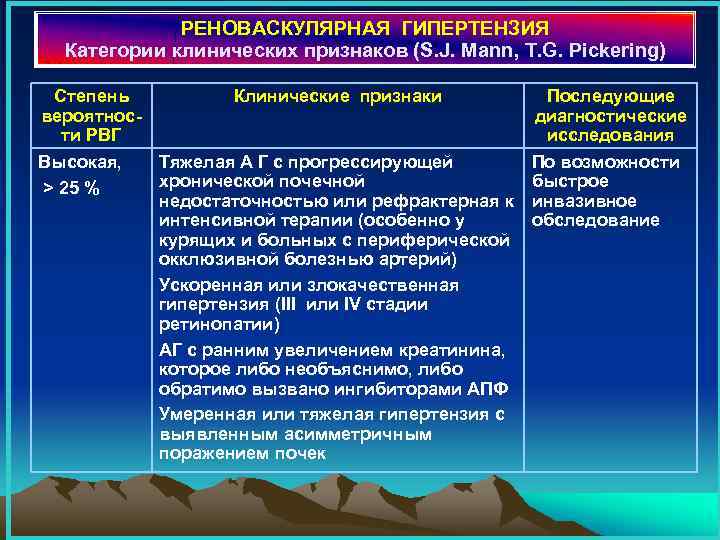

РЕНОВАСКУЛЯРНАЯ ГИПЕРТЕНЗИЯ Категории клинических признаков (S. J. Mann, T. G. Pickering) Степень Клинические признаки вероятности РВГ Высокая, Тяжелая А Г с прогрессирующей хронической почечной > 25 % недостаточностью или рефрактерная к интенсивной терапии (особенно у курящих и больных с периферической окклюзивной болезнью артерий) Ускоренная или злокачественная гипертензия (III или IV стадии ретинопатии) АГ с ранним увеличением креатинина, которое либо необъяснимо, либо обратимо вызвано ингибиторами АПФ Умеренная или тяжелая гипертензия с выявленным асимметричным поражением почек Последующие диагностические исследования По возможности быстрое инвазивное обследование

РЕНОВАСКУЛЯРНАЯ ГИПЕРТЕНЗИЯ Категории клинических признаков (S. J. Mann, T. G. Pickering) Степень Клинические признаки вероятности РВГ Высокая, Тяжелая А Г с прогрессирующей хронической почечной > 25 % недостаточностью или рефрактерная к интенсивной терапии (особенно у курящих и больных с периферической окклюзивной болезнью артерий) Ускоренная или злокачественная гипертензия (III или IV стадии ретинопатии) АГ с ранним увеличением креатинина, которое либо необъяснимо, либо обратимо вызвано ингибиторами АПФ Умеренная или тяжелая гипертензия с выявленным асимметричным поражением почек Последующие диагностические исследования По возможности быстрое инвазивное обследование